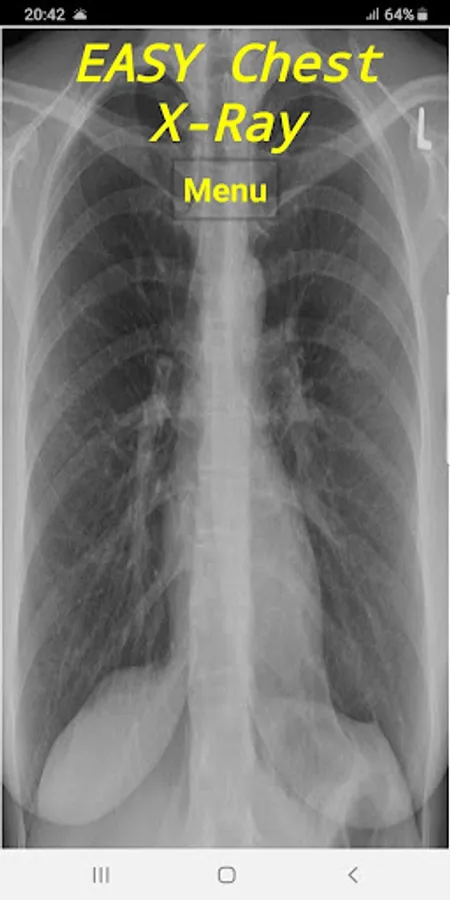

In brief, This application designed to have a quick review and interpret a Chest X-Ray in your daily practice. It covers the normal and most abnormal Chest X-Rays in an organized way to approach. It is recommended app for all ER doctors, general practitioners, Medical Students and who is interested.